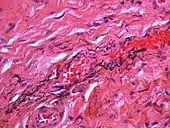

Silver sulfide deposits are found in proximity to small vessels in the oral mucosa

If necessary, the diagnosis can be confirmed histologically by excisional biopsy, which excludes nevi and melanomas.[3]:138 If a biopsy is taken, the histopathologic appearance is:[1]

• Pigmented fragments of metal within connective tissue

• Staining of reticulin fibers with silver salts

• A scattered arrangement of large, dark, solid fragments or a fine, black or dark brown granules

• Large particles may be surrounded by chronically inflamed fibrous tissue

• Smaller particles surrounded by more significant inflammation, which may be granulomatous or a mixture of lymphocytes and plasma cells